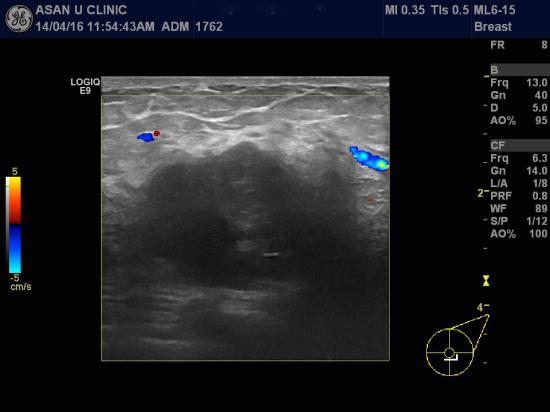

좌측 유방의 몽우리와 통증으로 내원한 55세 여성분입니다.

외부 유방촬영상 좌측 유방에 잡히는 몽우리와는

다른쪽에 미세석회화가 군집을 이루고 있고

본원 초음파로 확인한 유두근처 상내측에도 0.5cm미만의 조그만 혹이 있어

세군데를 각각 조직검사 시행하였습니다.

결과상 모두 침윤성 유관암으로 진단되어 치료위해 전원되셨습니다.